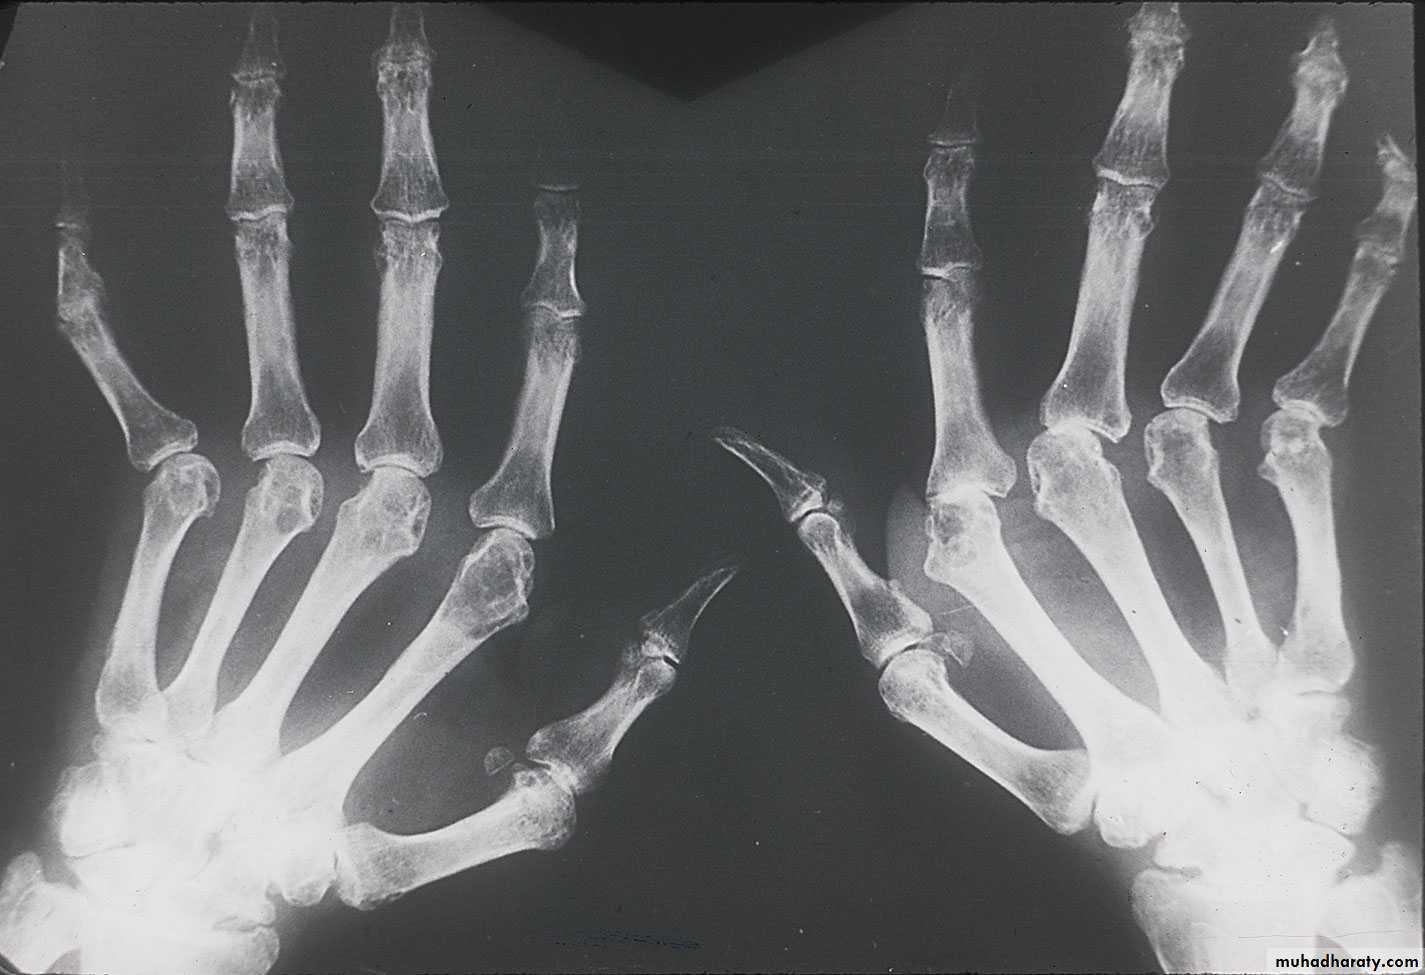

Provide a good reflection of disease activity. The typical features are symmetrical swelling of MCP& PIP joints. They are hot, tender & have stress pain on passive movement.Specific hand abnormalities include swan neck deformity, button hole (boutonnière) deformity& Z- deformity of thumb. Other abnormalities include :

dorsal subluxation of ulnar styloid of the wrist , trigger finger, cock up deformity of the toe, flatfoot, Baker's(popliteal) cyst which can be mistaken for DVT, but past history of joint disease & Doppler U/S can establish the diagnosis of DVT.

3- X-ray: the typical radiographic changes of RA are periarticular osteopenia& marginal non proliferative erosions.